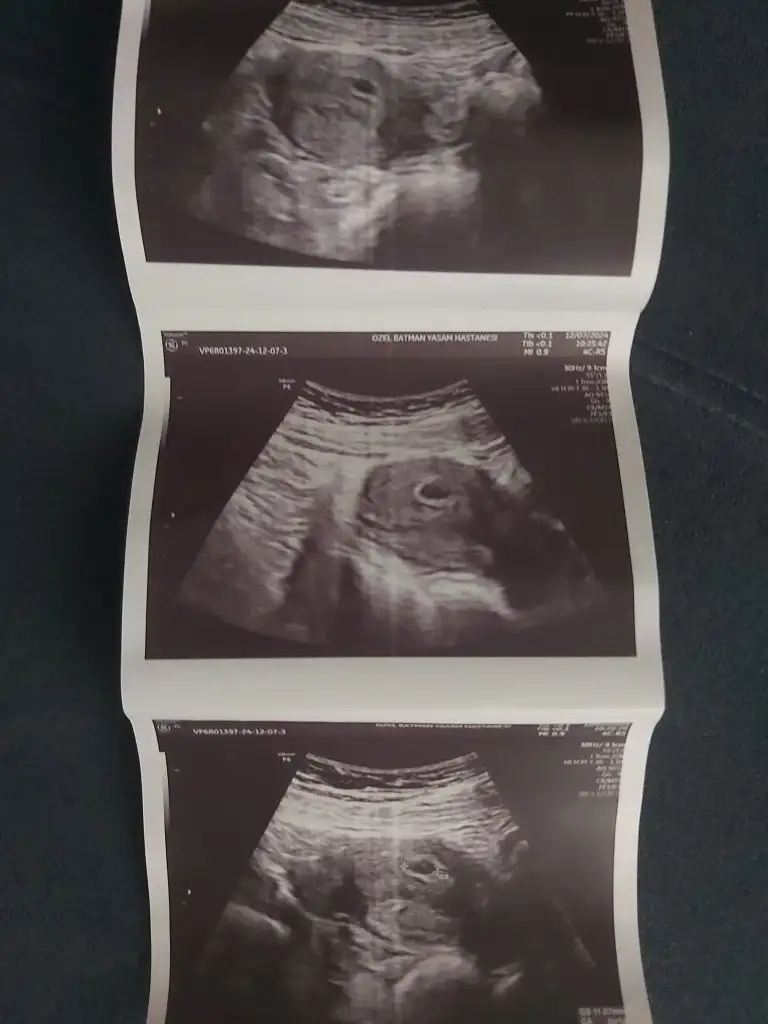

5+3’te ilk doktor muayenemi oldum karından ultrasonda çok çok küçük olduğu için alttan muayene oldum. Kese (8 mm ölçtü) ve yolk sac rahatlıkla göründü. Doktor son dakika bebeği de gördü ama ölçülemeyecek kadar küçük haftaya gel dedi.

Salı günü 2. Muayenede de alttan uzunca baktı. Dönüp 5+3 ile uyumlu crl 5.5 diye notlar aldırdı. Bana “bebek çok küçük geç döllenme olabilir bir şans daha verelim haftaya gel” dedi. Normalde 6+3 olması gerekiyordu adetime göre. Çok endişelendim açıkçası ve cumartesi günü özel hastanede iyi bir doktora randevu aldım.

Özel hastanedeki doktorum karından ultrasonla baktı sadece ve bebeği gördü hayırlı olsun 6+1 ile uyumlu dedi (SATa göre 7 olmalıydı). Kalp atışı var mı deyince yook daha çok küçük 10 gün sonra gelin dedi

Kese 12 mm yazıyor ultrason kâğıdında. Bilgisi olan birileri yorum yaparsa çok sevinirim sorun var mı yok mu bilmiyorum o kadar endişeliyim ki anlatamam

karından ultrason fotoğrafımı da yükledim lütfen sürecimi yorumlar mısınız